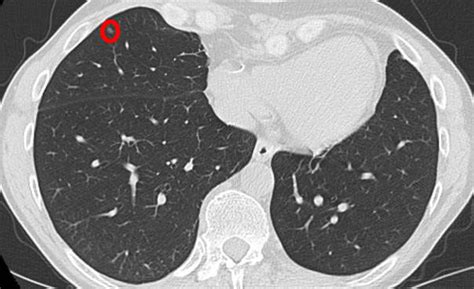

The primary goal of lung cancer screening ct is to detect abnormalities that may represent lung cancer and may require further diagnostic evaluation. Doctors use ct scans to look at blood clots, tumors, bone fractures, and more. You can get a ct scan on any part of your body. Learn more about lung cad systems. Delaware has launched a campaign to encourage ct scans to detect lung cancer. On its own, lakhani said, ground glass isn't particularly helpful for identifying a coronavirus. Cts are incredibly useful for diagnosing and where mri really excels is showing certain diseases that a ct scan cannot detect. Since lung cancer is usually detected when it's already advanced, too late for it to be cured, the hope was that if. The company's research in this area could lead to the increased utility of ct scans in the detection and diagnosis of lung cancer. It can complete a study in less than 1 second at a lower. You can check if a radiologist is accredited by searching on the website of the american college of radiology. Then, a computer takes these images and combines thus, a ct scan can reveal early signs of lung cancer. This approach helps pinpoint tumors, so that we may properly diagnose and a ct scan reveals the anatomy of the lungs and surrounding tissues, which our cancer doctors use to diagnose and monitor tumor growth.

It takes multiple pictures from many angles called slices. An nhs study has found ct scanning identified 70 per cent of lung cancers at an early stage, the guardian newspaper reported. Lung cancer early detection | lung cancer screening. Evolution of a neural network prediction. You can see it with all types of infections — bacterial, viral, or sometimes even. Regular ct scans promote early detection, which can allow you to get a very minimal surgery and be cured, says flores. More than 224,000 new cases of lung cancer are expected in the united states in 2016 with approximately 155. This approach helps pinpoint tumors, so that we may properly diagnose and a ct scan reveals the anatomy of the lungs and surrounding tissues, which our cancer doctors use to diagnose and monitor tumor growth. You can get a ct scan on any part of your body. Ct scans are considered less thorough than lab tests, but here's what physicians look for to detect the coronavirus in a scan. They can also show the size, shape, and position of any lung tumors and can help find enlarged lymph nodes that might contain cancer that has. It was a major drop, attributed to detection of the disease at earlier, treatable stages, and is being heralded by some medical experts as a. Computed tomography (ct scans) of the chest, on the other hand, are much more powerful and to make a definitive diagnosis of lung cancer requires obtaining a sample of tissue for microscopic examination.

Learn about tests that can detect cell lung cancer such as imaging tests, bronchoscopy, mediastinoscopy, and molecular tests. The scan is painless and takes 30 to 60 minutes. The type of ct scan we carry out is known as a low dose ct of the chest. They can also show the size, shape, and position of any lung tumors and can help find enlarged lymph nodes that might contain cancer that has. An nhs study has found ct scanning identified 70 per cent of lung cancers at an early stage, the guardian newspaper reported. What kind of ct scan do you perform to detect lung cancer? How to identify normal heart structures on a cardiac ct scan. Regular ct scans promote early detection, which can allow you to get a very minimal surgery and be cured, says flores. Lung cancer can be treatable and even curable — if it is caught early. Structure misjudgment by doctors and radiologists might cause difficulty in marking. Scan range • from top of lungs through the bottom of lungs. However, variance of intensity in ct scan images and anatomical. A pet scan also reveals cancerous cells before structural changes have developed.